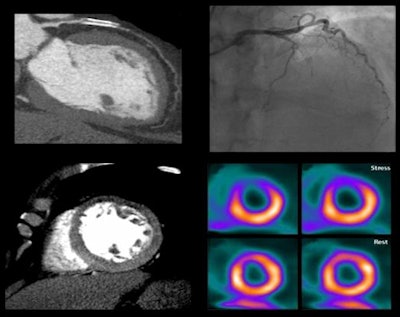

Image of CORE320 patient shows an occluded left anterior descending (LAD) stent on CT and catheterization, with the corresponding anterior wall defect demonstrated by CT perfusion and SPECT. Image courtesy of CORE320 investigators.The value of CT perfusion

"The reference standard for a hemodynamically significant lesion is a lesion that's seen on catheterization that causes a perfusion abnormality on SPECT," he continued. "We put cath and SPECT together [with CTA-CTP] so you could actually say for sure that the lesion was hemodynamically significant."

Previous studies performed in one or two centers have demonstrated the value of CT perfusion combined with CTA, but the results have not been compared with comprehensive reference standards, Rybicki said. As a result, CORE320 was designed to test the hypothesis that noninvasive CTA-CTP could reliably detect or exclude the presence of flow-limiting coronary stenoses in patients with suspected coronary artery disease (CAD), using a strong composite reference standard of invasive coronary angiography plus SPECT/MPI.

For detecting or excluding flow-limiting coronary artery disease, combined CTA-CTP showed an area under the curve (AUC) of 0.87 for all patients. In patients without prior myocardial infarction, AUC was even higher at 0.90, and in patients without any prior coronary artery disease, AUC was 0.93. For a patient with 50% or greater stenosis and a perfusion deficit at CTP, the sensitivity and specificity of CTA-CTP were 80% and 74%, respectively.

Meanwhile, the prevalence of obstructive CAD defined by angiography and SPECT was 38%; by angiography alone, prevalence was 59%. The median radiation dose was 11 mSv for the combined CTA-CTP tests, according to Rybicki, who said that detailed radiation exposure results will be available in an upcoming publication.

Combined CTA-CTP underestimated coronary artery disease in 29 patients (false-negative results) and overestimated CAD in 61 patients (false-positive results), compared with the combined outcome of angiography and SPECT, the group reported.